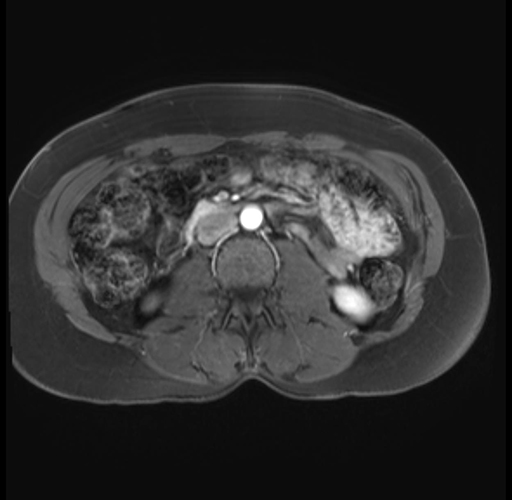

Imaging Analysis

Look through the patient's CT scan to identify any areas of concern for the necessary procedure.

Based on your CT findings, which issue(s) are present and would give reason for "planned slowing down moment(s)" in this case?